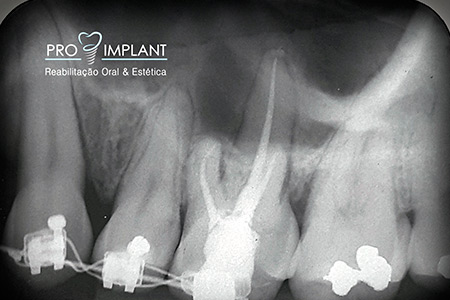

FOTOS

Endodontia